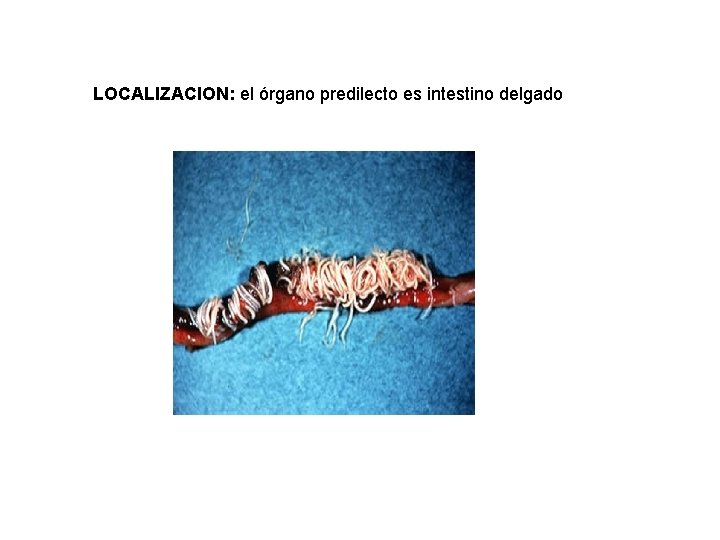

LOCALIZACION: el órgano predilecto es intestino delgado

PATOGENIA Número de vermes Edad y resistencia de los pollos Nivel de nutrición. Congestión y hemorragias determinando una enteritis hemorrágica en las infecciones intensas o una enteritis catarral en las más moderadas. Las hemorragias intestinales dan lugar a anemia y a alteraciones de la absorción intestinal.